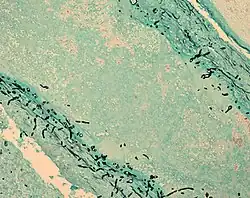

Fungal cells (black lines) in infected brain tissue (cyan)